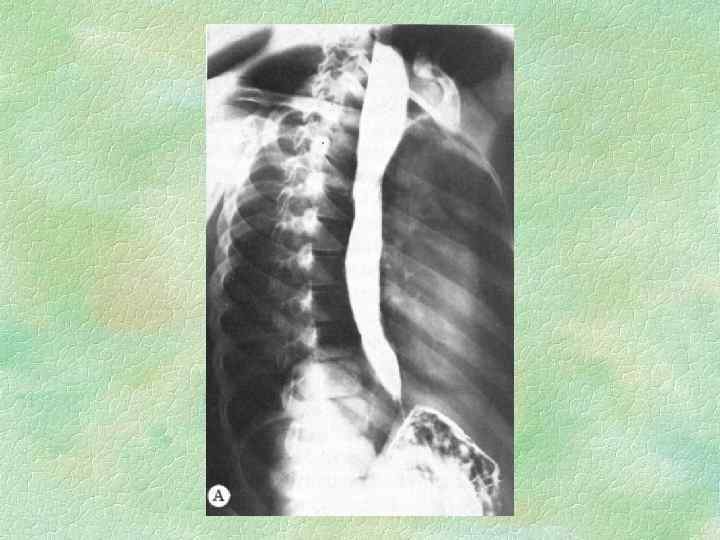

СТАДИИ КАРДИОСПАЗМА (Б. В. Петровский, 1962) I II IV непостоянный функциональный спазм без расширения пищевода постоянный спазм с незначительным расширением пищевода рубцовые изменения и органический стеноз с выраженным расширением пищевода резкий стеноз, удлинение и S-образная деформация пищевода